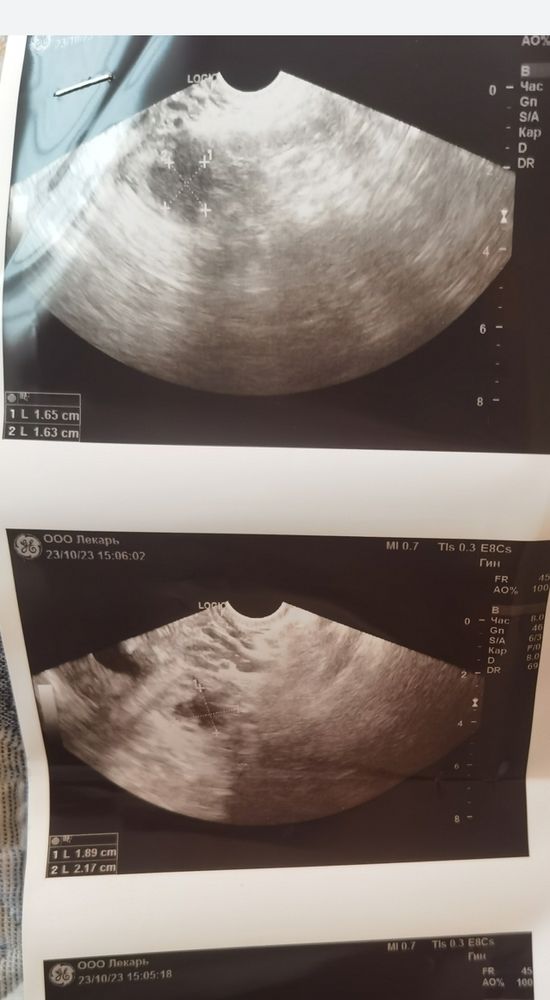

Киста или жт?

Больше на жт похоже

Жт